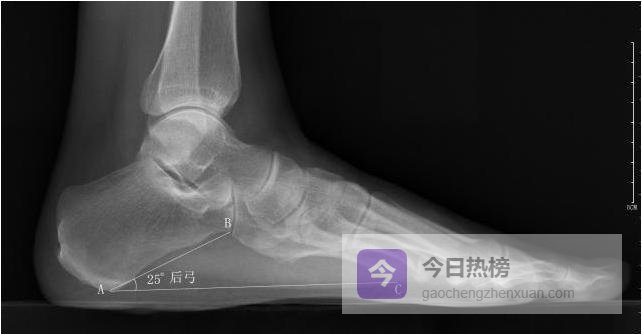

4.2.4 ◆ 后弓角 以跟骨最低点为原点,向跟骰关节最低点与第5跖骨头最低点各引一条水平线, 测量两线夹角。

后弓角<16°。